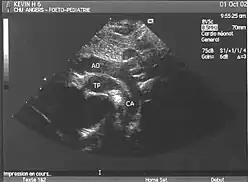

- La coupe parasternale gauche grand axe : elle montre que le vaisseau issu du ventricule gauche (le plus postérieur) se dirige anormalement vers l'arrière et se bifurque précocement. C'est donc le tronc pulmonaire et non l'aorte comme normalement.